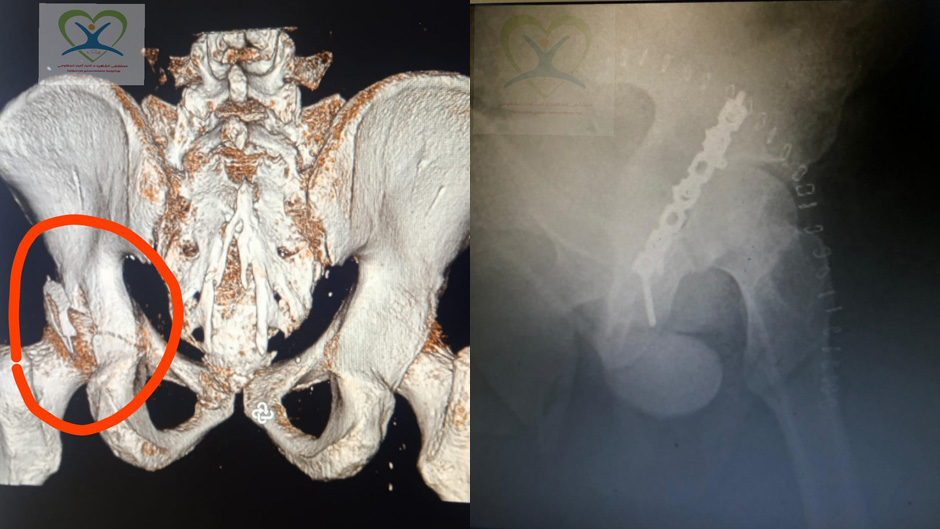

ونتيجة للعمل المتواصل والجهود المستمرة والمبذولة من قبل إدارة المستشفى وعلى رأسها مدير عام المستشفى هيثم شديد لتطوير الخدمات الطبية المقدمة للمواطن الكرمي وبجهود الطواقم الطبية العاملة وخاصة طواقم جراحة العظام وأطباء التخدير وطاقم قسم العمليات في المستشفى، فقد تم إجراء إحدى العمليات المعقدة في علاج كسور مفصل الحوض بنجاح تام قبل أيام لرجل خمسيني كان قد تعرض لإصابات متعددة بسبب الوقوع من علو، حيث أصيب بكسر معقد في إحدى عظام مفصل الحوض مع وجود قطعة عظمية داخل المفصل نفسه وكسور متعددة في الأضلاع وتعد هذه الحاله من الحالات الصعبة تخديريا أيضاً، حيث تم تحضير المريض لعدة أيام حتى استقرت حالتة الصحية العامة بسبب سوء التنفس لوجود عدة كسور في الأضلاع.

من ثم أجريت له عمليه جراحية من قبل اختصاصيي جراحة العظام الدكتور مثقال علوشي والدكتور خالد بواقنة استمرت لعدة ساعات، تم تثبيت الكسر بقطعة من البلاتين والبراغي وكذلك تم إزالة القطعة العظمية من المفصل. والآن المريض يتماثل للشفاء بعد نجاح تلك العملية.